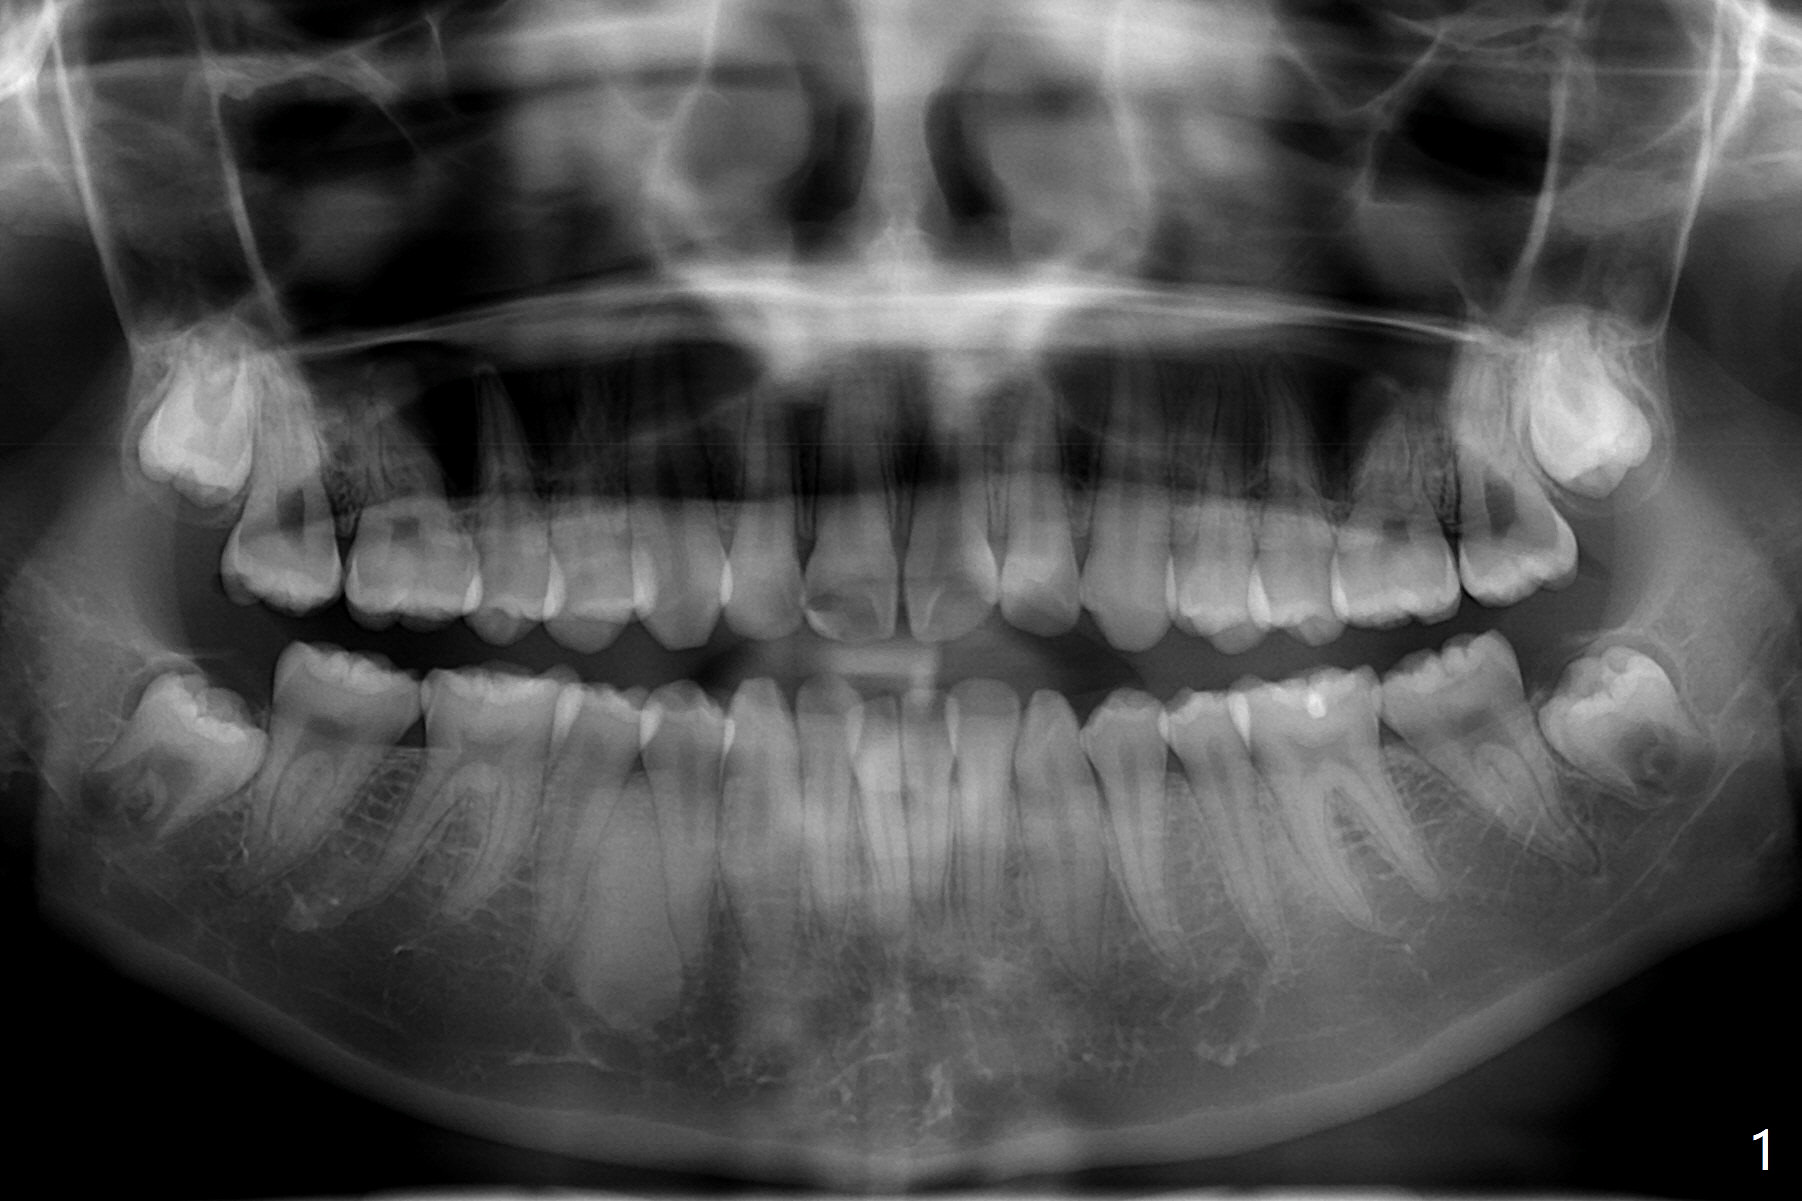

CT is taken 4 months post panoramic X-ray (Fig.2).  C: coronal; S: sagittal; A: axial; B: buccal.  Coronal (Fig.6) and sagittal (Fig.7) sections.  It seems that the lesion does not invade the thin buccal plate or the periodontium.